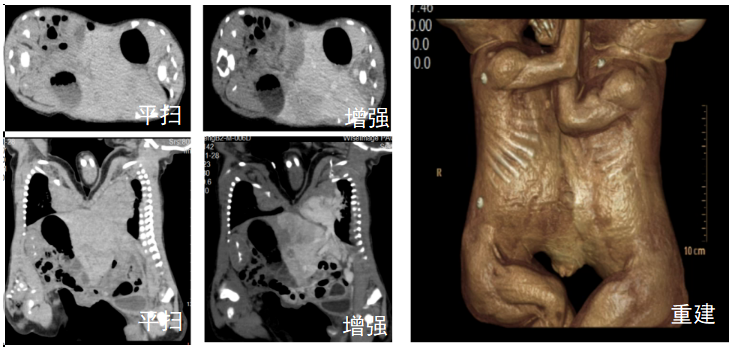

用于复杂病例(如连体婴评估),指导手术方案。

CT增强扫描应用于临床手术方案制定(连体婴)

CT增强扫描应用于临床手术方案制定(肝肿瘤术前方案制定)